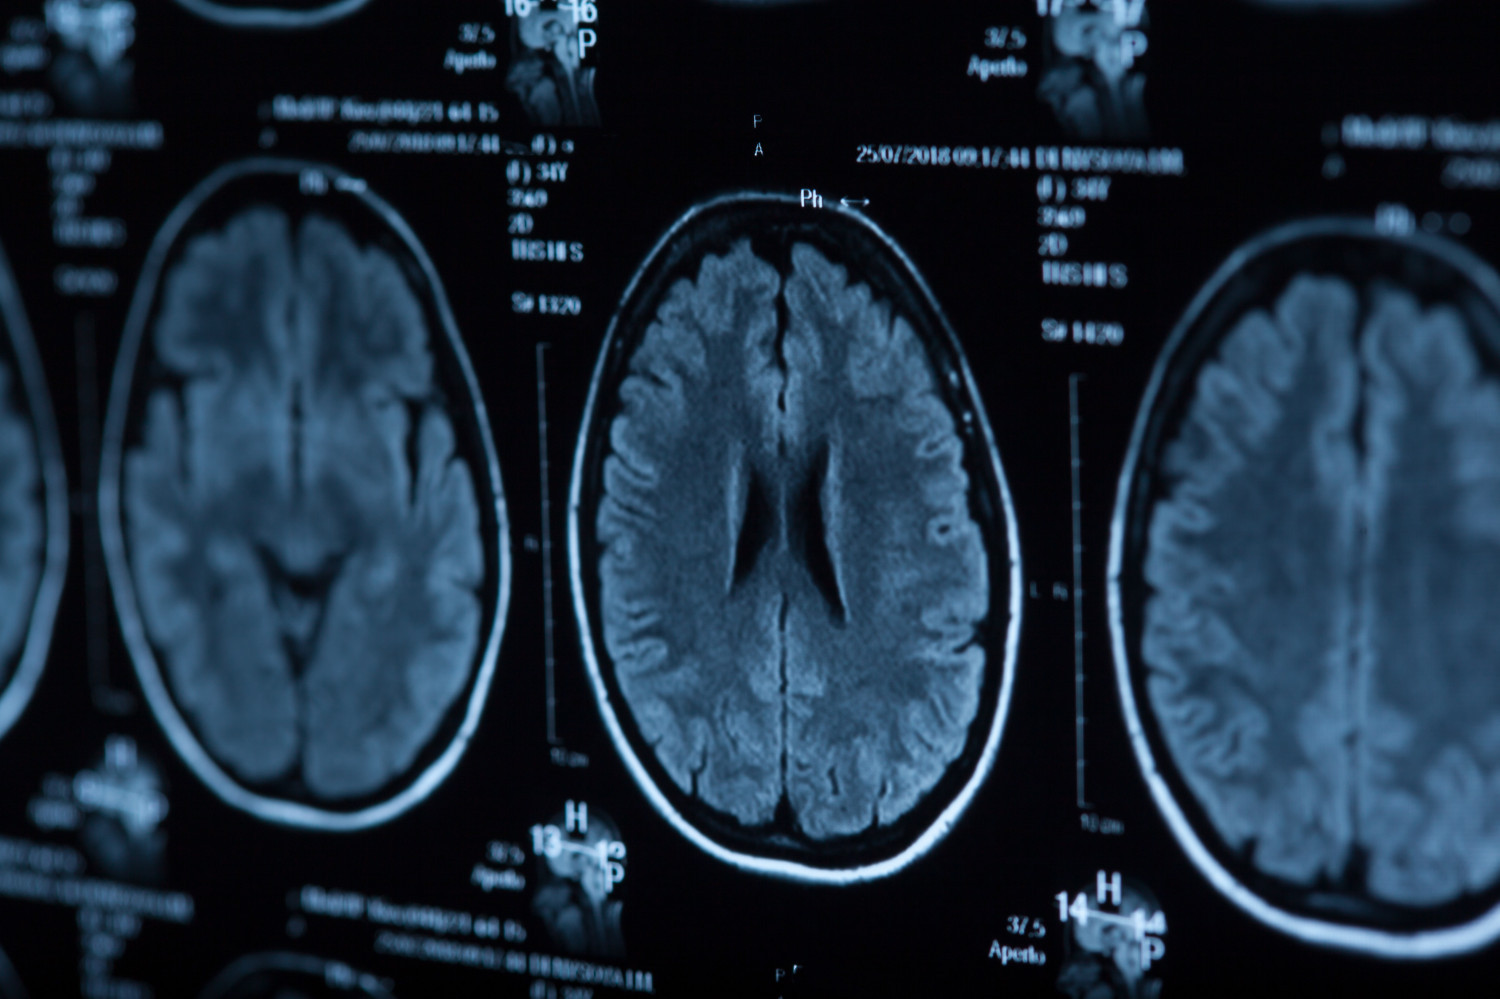

Исследователи оценили влияние антитромбоцитарной терапии на риск симптоматического внутричерепного кровоизлияния у пациентов с инсультом после тромболизиса. Результаты исследования опубликованы в JAMA Neurology.

Симптоматическое внутричерепное кровоизлияние наблюдалось у 2,9% пациентов, не получавших антитромбоцитарную терапию, у 3,8% принимавших антитромбоцитарную монотерапию и у 4,1% участников, получавших двойную антитромбоцитарную терапию.

У пациентов, получавших антитромбоцитарную монотерапию, риск оказался на 13% выше, а у пациентов на двойной антитромбоцитарной терапии — на 28% выше по сравнению с теми, кто не принимал такие препараты. Однако ученые отметили, что в абсолютных цифрах повышение риска небольшое: на 0,9% для монотерапии и 1,2% для двойной терапии.

| В исследовании участвовали 321 819 пациентов, которых госпитализировали по поводу острого ишемического инсульта. Средний возраст участников составил 69 лет. Участникам назначали внутривенный тканевой активатор плазминогена в течение 4,5 часа после появления симптомов. |

Исследователи подчеркивают, что нахождение на двойной антитромбоцитарной терапии не должно исключать тромболитическую терапию, если она показана, поскольку преимущества такого лечения перевешивают возможный риск осложнений.